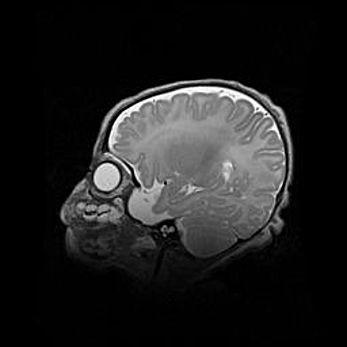

Сообщающаяся гидроцефалия. Кистозная энцефаломаляция головного мозга.

Возраст: 3 месяца 4 дня

Вес: 3100 г

Пол: женский

Окружность головы: 34 см

Срок гестации: 31 неделя

Кистозная энцефаломаляция головного мозга - одна из форм поражения головного мозга в детском возрасте. Характеризуется возникновением множественных и распространённых кист в коре, белом веществе и подкорковых образованиях головного мозга у плодов, новорождённых и детей раннего возраста. Развитие кистозной энцефаломаляции связано с внутриутробной асфиксией и гипотонией, родовой травмой, тромбозом синусов, пороками развития сосудов, инфекциями, сепсисом и другими причинами. Наиболее значимые инфекционные агенты: вирусы простого герпеса, цитомегалии, краснухи, токсоплазмы, энтеробактерии, золотистый стафилококк и другие.